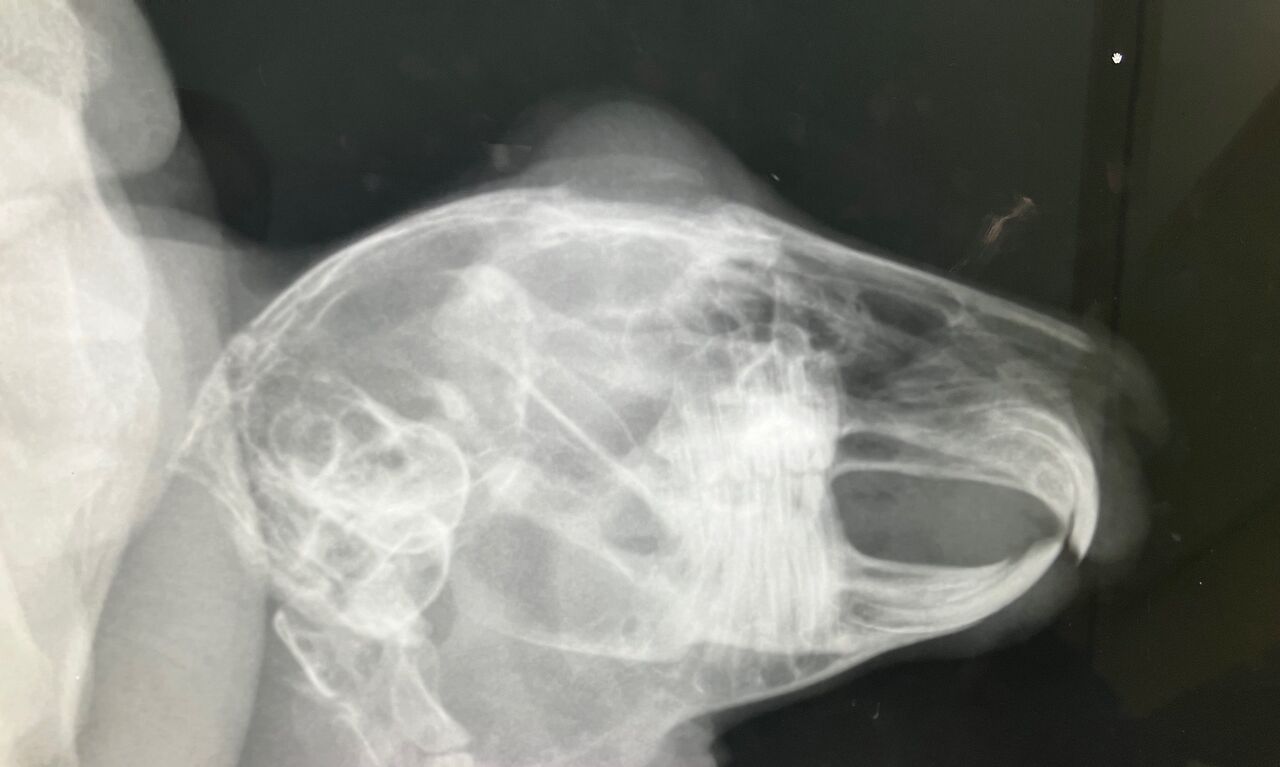

そして11月27日、避妊手術

術前の血液検査、レントゲン、特に問題ありませんでしたが、

口内検査で歯、奥歯右下3番目が少し内側に向いてたのでカット処置。